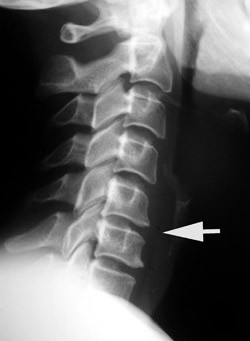

At selv en dokumentert, eldre skade kan være uten symptomer, skulle være velkjent. At de degenerative forandringene progredierer likeså. Og – ja visst – det går svært langsomt, for osteogenesen er en sendrektig prosess, og ofte synes ikke nydanningene – forårsaket av en periostal reaksjon – før etter 5 – 10 år. Jeg vedlegger eksempelvis to bilder av en pasient, tatt med sju års mellomrom. Vedkommende hadde nakkesmerter, men benektet traume, inntil et fall noen måneder tidligere ble nevnt. Det første bildet (fig 1) ble beskrevet som «normalt», tross kyfotisk knekk og antydet skivereduksjon C5 – 6 (pil). Det andre bildet (fig 2) viser resultatet av denne «ubetydelighet», den gang med atskillige plager, i dag med tilnærmet symptomfrihet – dog med langtkommet spondylose og ytterligere reduksjon av skiven.